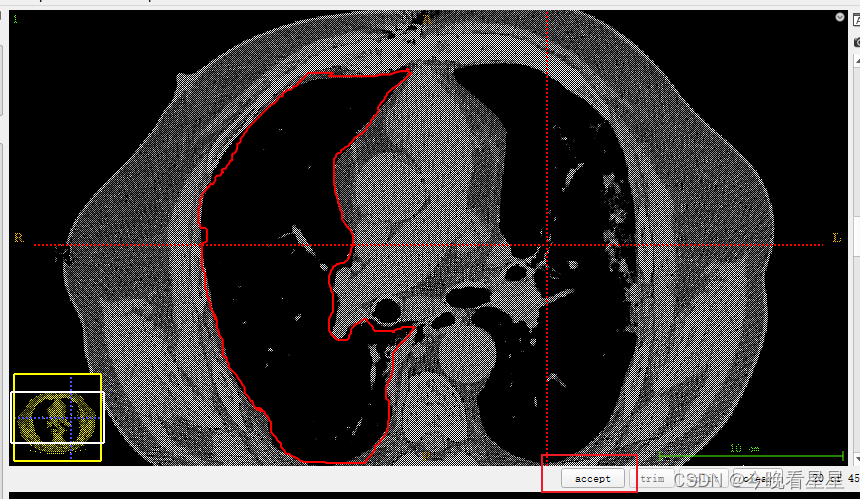

- 使用画笔工具进行涂画,选择不同的大小进行边界以及内容的填充,选择边界自适应填充可以根据不同的CT值,来填充不同的区域

- 自适应画笔的效果

- 最终的效果